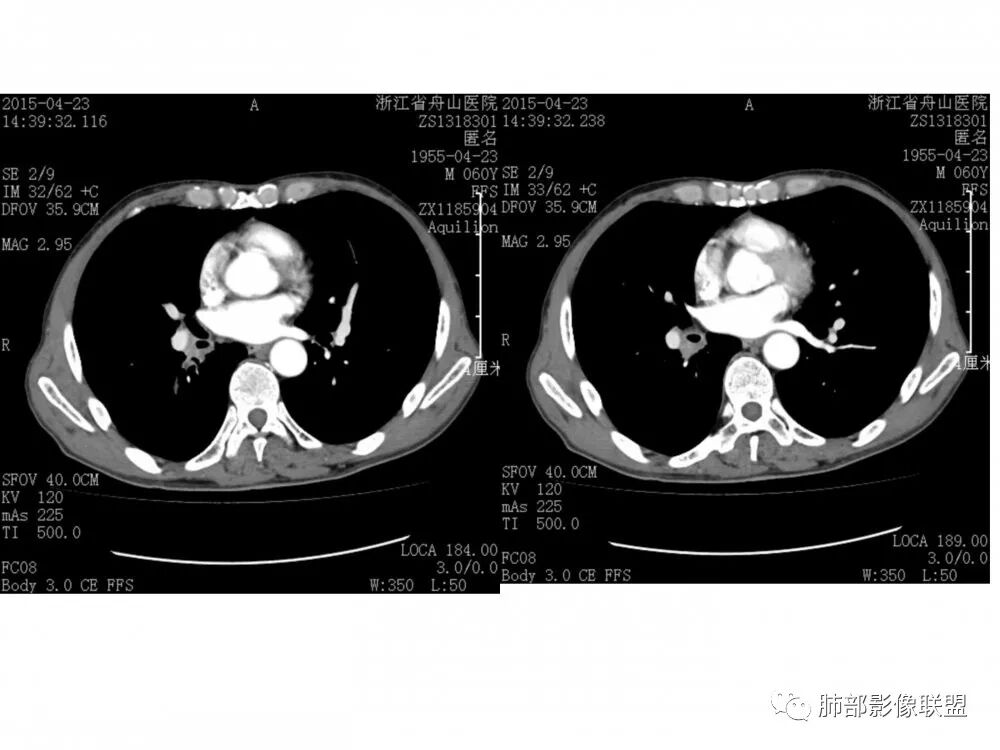

右肺下叶支气管开口新生物,轴位管腔及纵向基底干大部分受累狭窄,支气管管壁破坏明显,强化较低不均匀,肺门、7组、4R淋巴结肿大,考虑恶性支气管腔内肿瘤,鳞癌可能性大,需要与类癌、涎腺类肿瘤鉴别

老年男性,60岁,右下肺门肿块,右下支气管粘膜下生长,并堵塞,无明显阻塞性肺炎和肺不张,早期多发淋巴结转移,似不均匀强化。综合看恶性程度高,考虑大细胞癌,一个不支持点,大细胞癌外周多见。

优先需要与小细胞癌鉴别,再鳞癌鉴别。肿瘤恶性程度排序,小大腺鳞类。小细胞癌不支持点是:1.沿着支气管粘膜下生长,支气管阻塞轻,爬行征;2.包绕血管,冰冻纵隔,有可能病灶比较小,所以没那么快包裹;这例这点不符合。其他倒是符合中央型小细胞癌,比如转移早,恶性程度高。

男,60岁,右肺下叶支气管开口新生物,轴位管腔及纵向基底干大部分受累狭窄,支气管管壁破坏并突破形成腔外肿块,强化较低不均匀,右肺门、7组、4R淋巴结肿大,考虑恶性没问题,鳞癌可能性大,类癌、粘液表皮样癌,乳头状瘤待排。

右肺下叶支气管不规则软组织肿块,病灶沿支气管生长,有一定的张力,部分包绕支气管壁,增强病灶内可见中度强化,内部有延迟强化的特点,周围淋巴结增大,诊断恶性病变无疑,远端无明显支气管阻塞,主要考虑粘液表皮癌,腺样囊腺癌,鳞癌之间鉴别,病灶有类似神经源性病变生长方式,腺样囊腺癌,其次考虑鳞癌或粘液表皮癌。